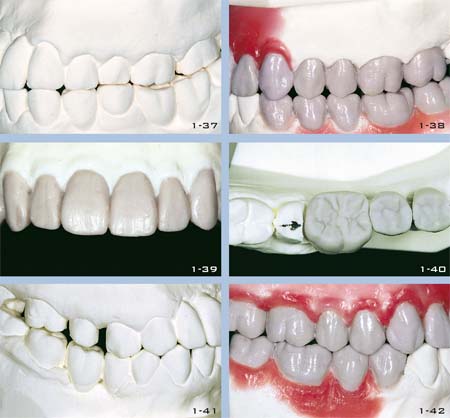

Oft ist es schwierig, Ästhetik und Präzision gleichzeitig zu erzielen. Häufig wird eher die Ästhetik angestrebt als die Präzision oder umgekehrt. Vertreter der Ästhetik behaupten oft, dass für die Gesundheit des Parodonts gar keine exzessive Präzision erforderlich sei. Die Anhänger der Präzision preisen dagegen die Tugenden von Gold, dem einzigen Material, das präzise Ränder garantieren kann (Abb. 18 und 19).

Abb. 18 und 19 Randspalt bei einer Metallkrone (18) und einer Vollkeramikkrone ohne verstärkenden Core (19). Diese Unvollkommenheit ist so gering, dass sie mit Zement ausgefüllt werden kann. Allerdings ist der Zement dem Speichel ausgesetzt, was kurz- oder mittelfristig zu einem Misserfolg führen kann, je nach Zementierungstechnik und -material.